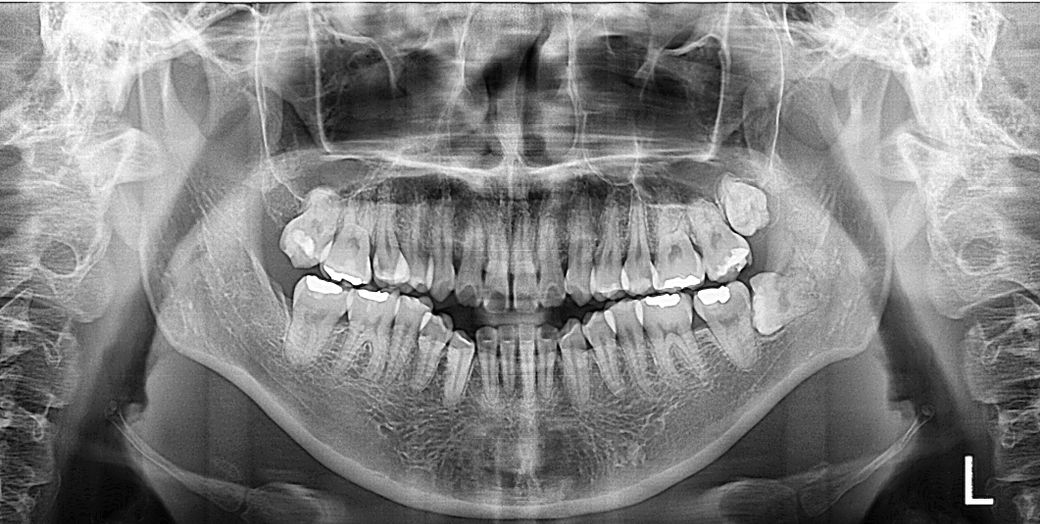

발치 예정 치아 뿌리가 상악동 닿아 천공 발생할지 엑스레이 판단 부탁드립니다

안녕하세요 교정발치로 윗니 5번 발치 예정입니다

제가 보기엔 둘 다 뿌리가 상악동과 맞닿아 있고 특히 왼쪽 5번 윗니가 상악동과 바로 붙어있어 보입니다

전문가분들이 보시기에 어떤지 말씀 부탁드립니다ㅠㅠ

뿌리가 상악동과 맞닿아서 발치시 천공이 우려됩니다ㅠㅠ